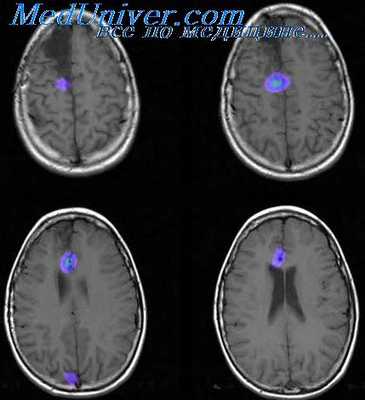

Выявление морфологического субстрата, лежащего в основе фокальной эпилепсии, производится путём МРТ. Для выявления малейших структурных изменений исследование должно проводится с малой толщиной срезов (1-2 мм). При симптоматической эпилепсии МРТ головного мозга позволяет диагностировать основное заболевание: очаговое поражение, атрофические и диспластические изменения. Если отклонения на МРТ не были выявлены, то устанавливается диагноз идиопатическая или криптогенная фокальная эпилепсия. Дополнительно может проводиться ПЭТ головного мозга, которая выявляет участок гипометаболизма церебральной ткани, соответствующий эпилептогенному очагу. ОФЭКТ на этом же участке определяет зону гиперперфузии во время приступа и гипоперфузии — в период между пароксизмами.

Установить причину, по которой возникла височная эпилепсия, во многих случаях помогает МРТ головного мозга. Наиболее частой находкой при ее проведении является медиальный височный склероз. С помощью МРТ также можно диагностировать кортикальные дисплазии, опухоли, сосудистые мальформации, кисты, атрофические изменения височной доли. ПЭТ головного мозга при височной эпилепсии обнаруживает снижение обмена веществ в височной доли, зачастую затрагивающее таламус и базальные ганглии.